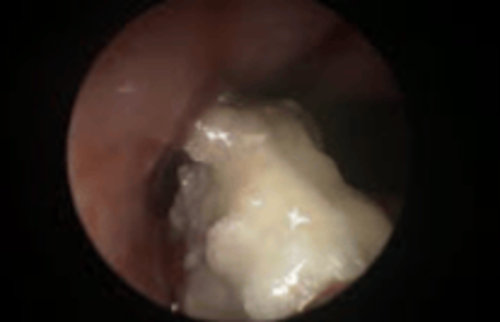

Pilzplaque